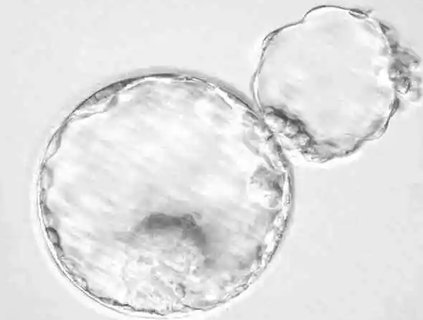

2024-08-02輔助孵化是輔助生殖技術(shù)中的一種微侵入性操作,旨在幫助胚胎更容易孵化并附著于子宮內(nèi)膜。許多準(zhǔn)備進(jìn)行試管嬰兒的患者都關(guān)心這一技術(shù)是否能夠提高成功率。